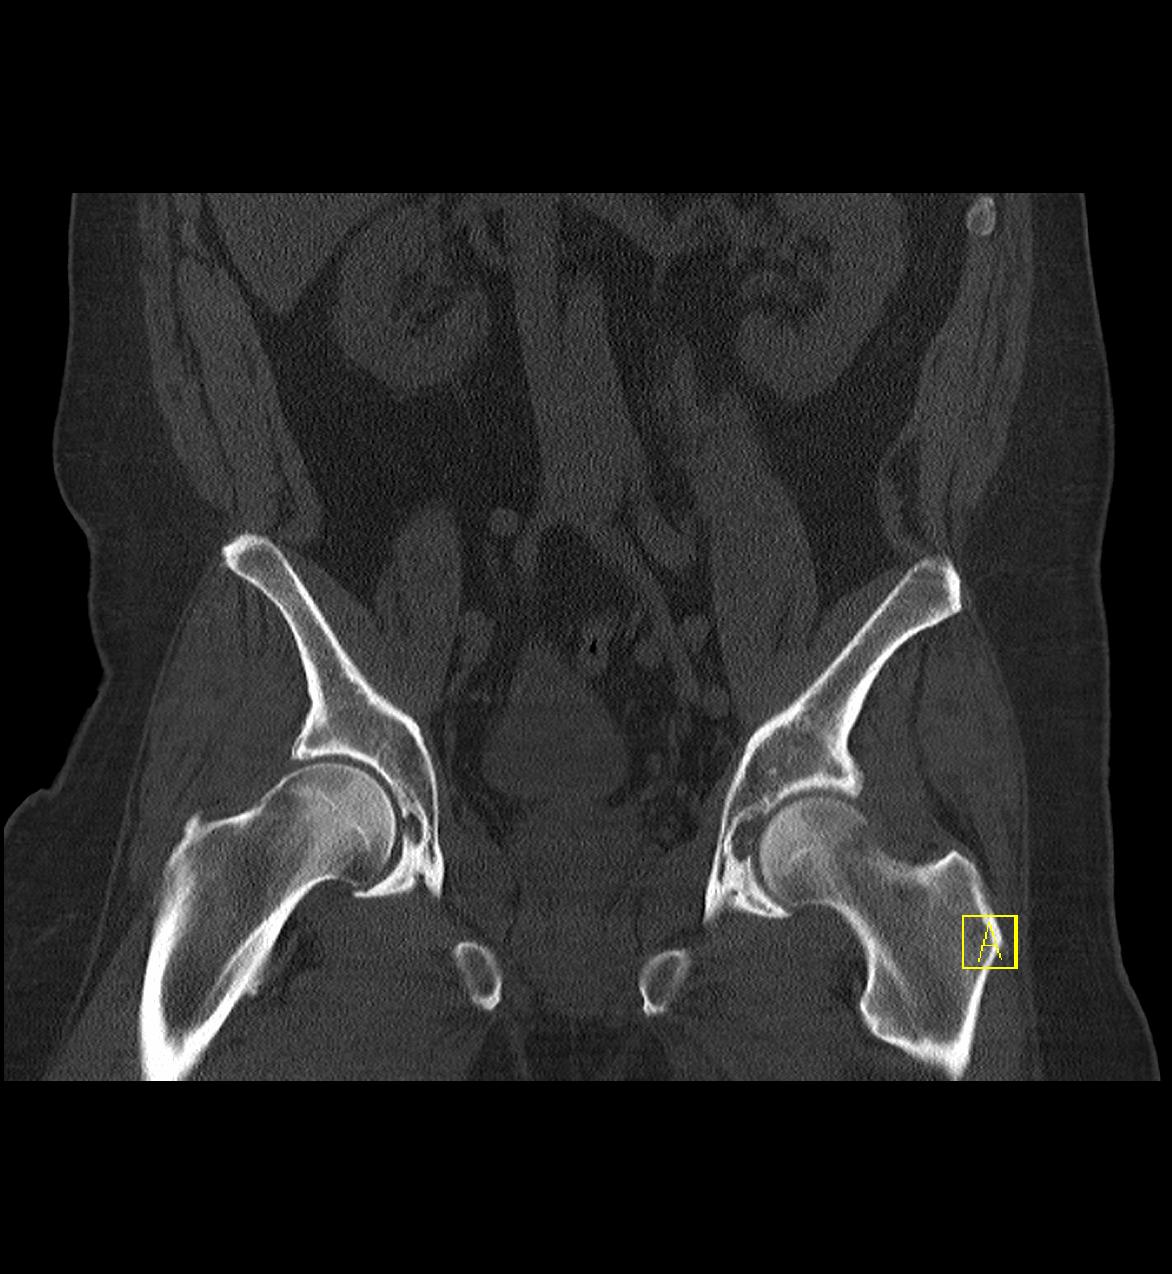

Bei Untersuchungen vom Becken sind keine speziellen Vorbereitungen notwendig. Nur selten wird auch eine intravenöse Kontrastmittelgabe erfolgen. Manche Erkrankungen erfordern eine Kontrastmittelgabe über den Enddarm, hierfür müssen Sie zu Hause aber keine besonderen Vorbereitungen treffen. Dabei wird Ihnen über ein Darmrohr ein Liter verdünntes jodhaltiges vorgewärmtes Kontrastmittel verabreicht, nachdem der Arzt den Enddarm untersucht hat.

Die Untersuchungszeit beträgt ca. 10-20 Minuten.